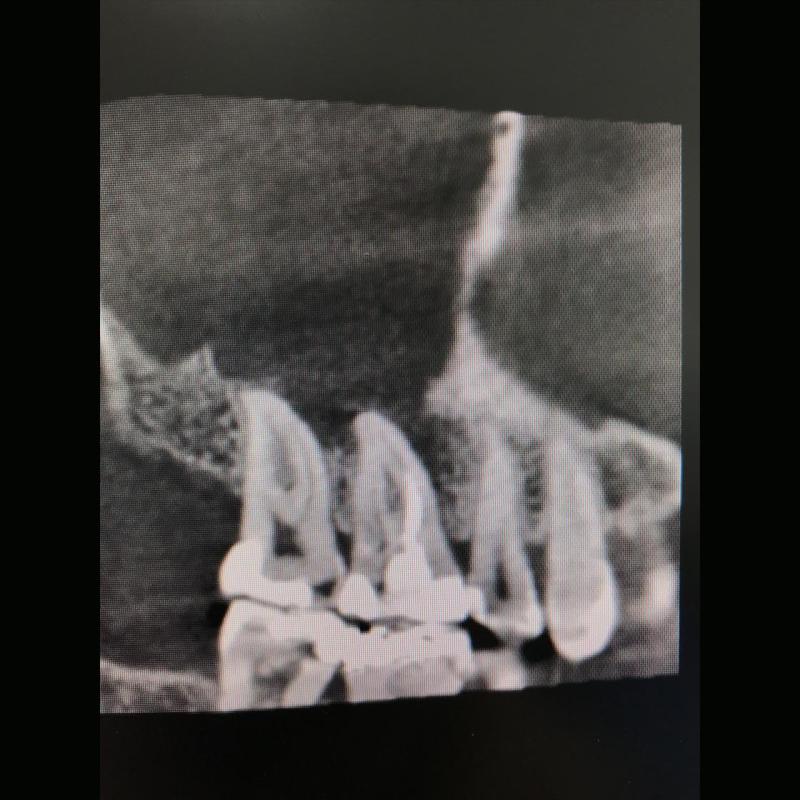

Lo Studio Zambon dispone di apparecchiature di ultima generazione, anche in campo diagnostico, come la Tac 3D Cone Beam, utilizzata in chirurgia, endodonzia e parodontologia, che consente una visione in 3D della struttura ossea e garantisce dosi radianti ridotte.

La parodontologia controlla il benessere delle strutture portanti dei denti (gengive e osso di sostegno) cercando di prevenire o curare la piorrea che nella popolazione adulta è la più frequente causa di perdita dei denti.

Oggi più che mai viene richiesta la copertura di esposizioni radicolari mediante la chirurgia estetica mucogengivale. Inoltre con la cura della piorrea si mantiene in buono stato la salute generale del paziente prevenendo complicanze cardiovascolari e diabetiche.